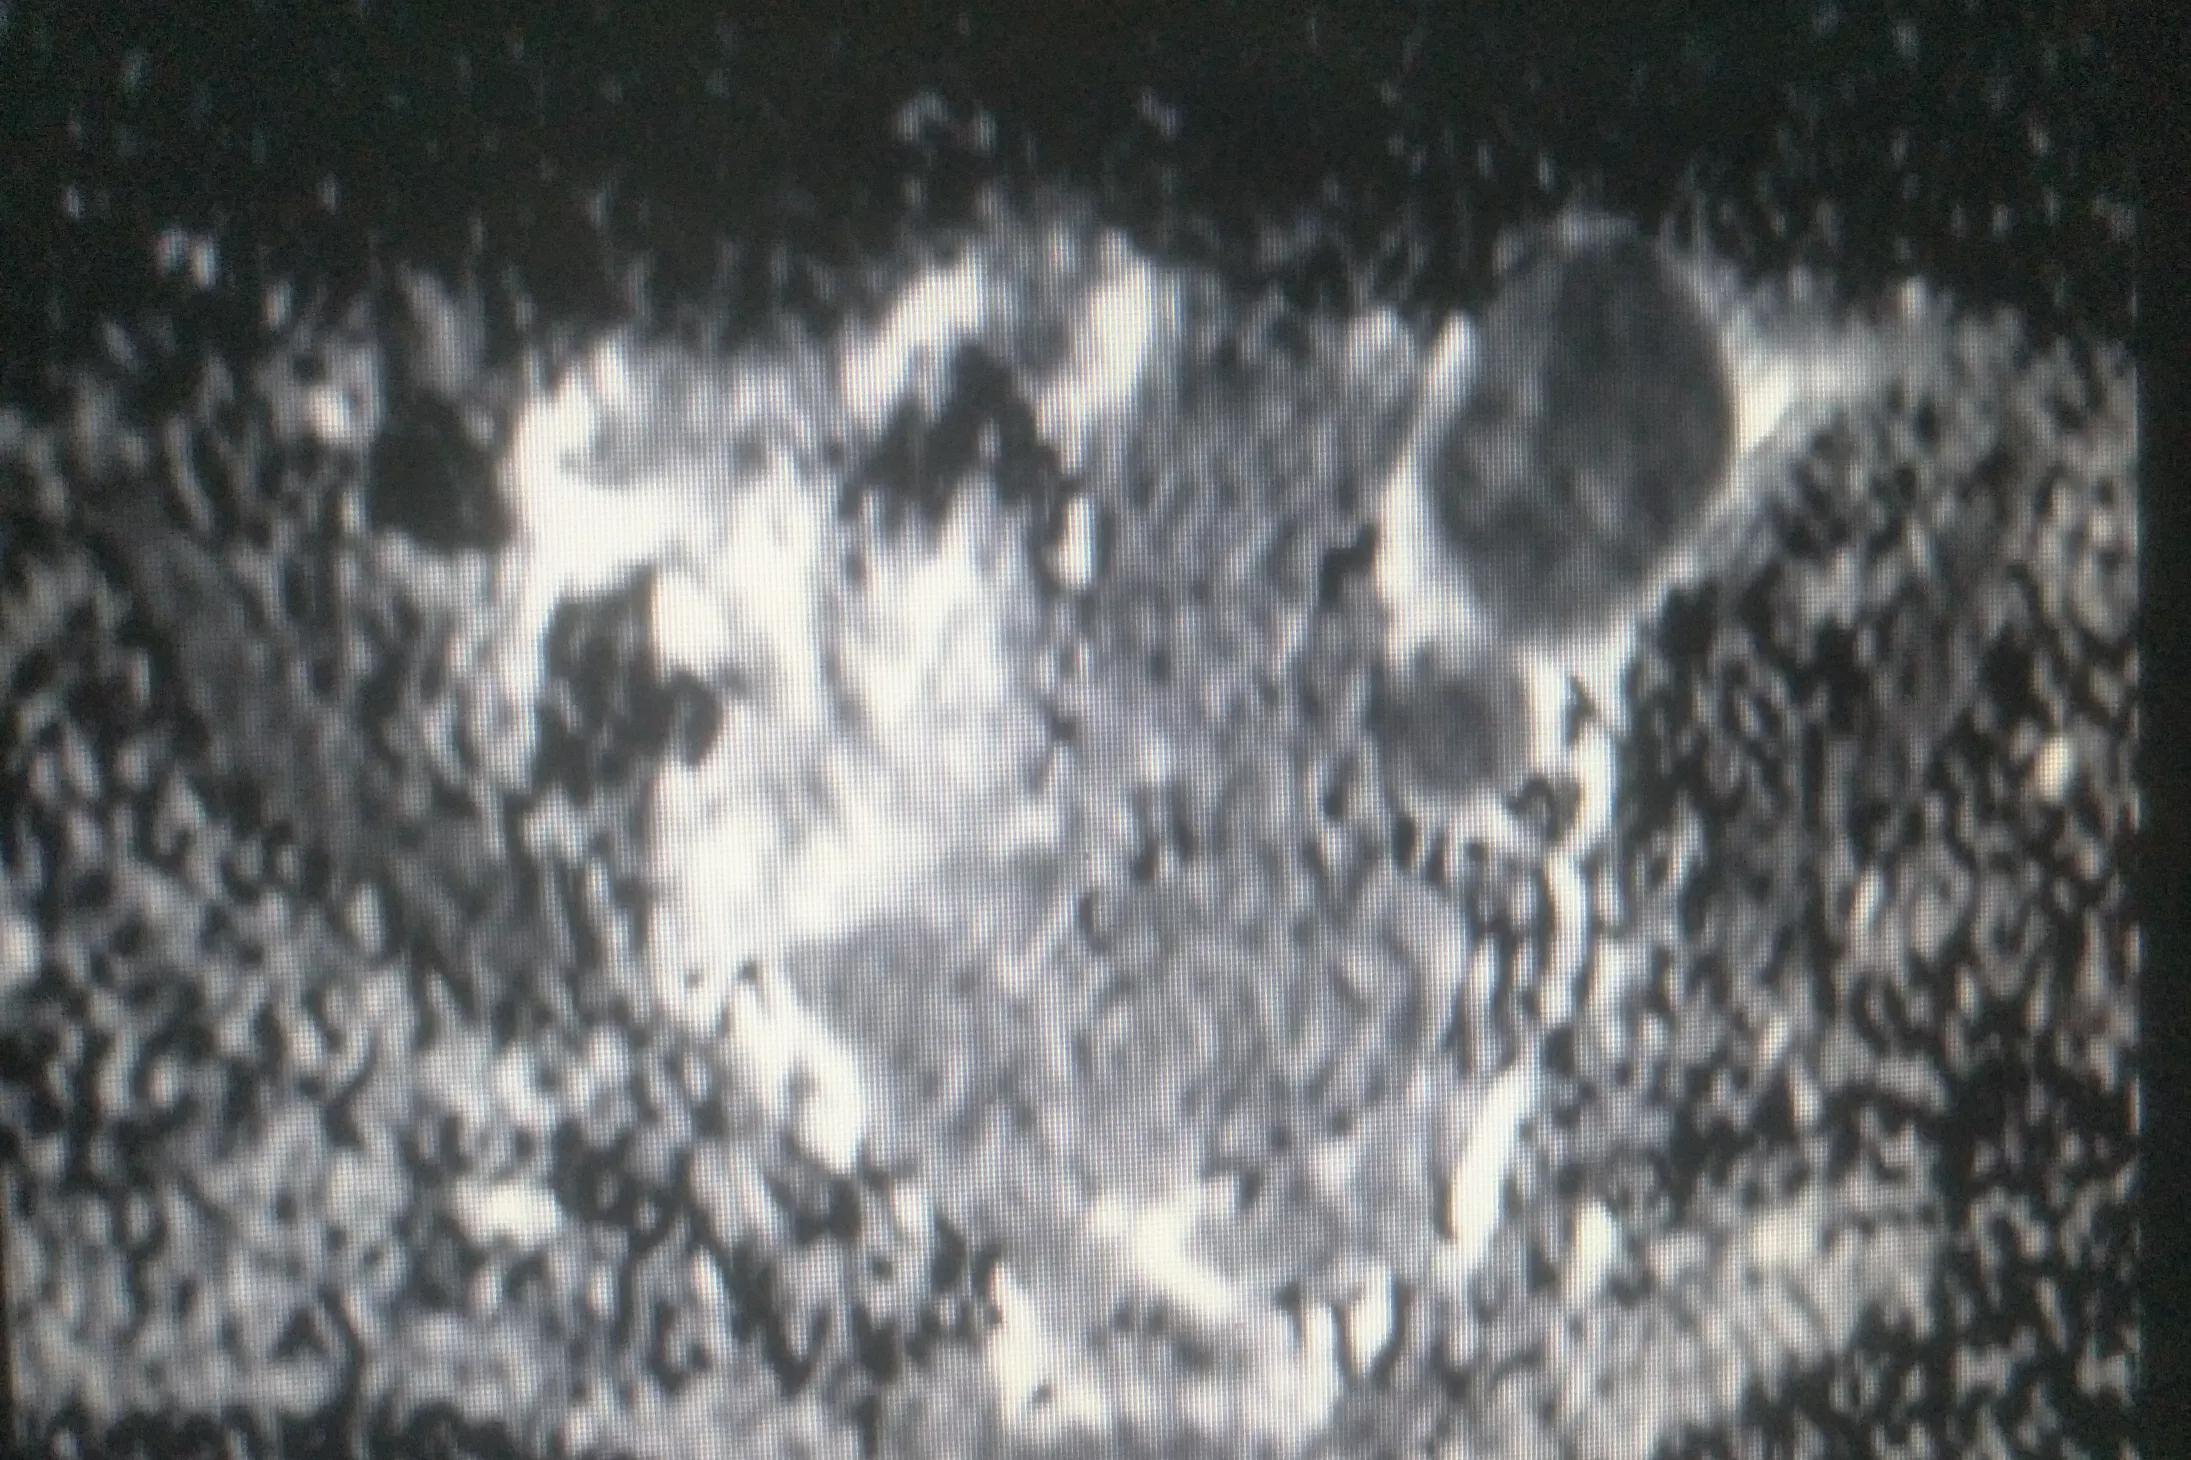

果真,在接下来的彩超及核磁共振检查中均提示为恶性肿瘤。

肿大淋巴结的超声图像,血运非常丰富。

肿大淋巴结的MRI图像